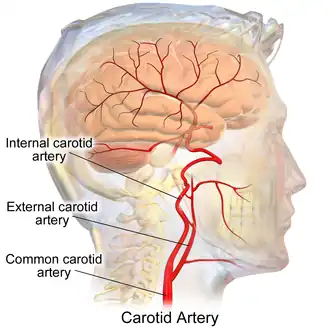

Arteries of the neck. The internal carotid arteries arise from the common carotid arteries - labeled Common caroti on the figure. | |

The internal carotid artery is an artery in the neck which supplies the anterior and middle cerebral circulation.[1]

In human anatomy, the internal and external carotid arise from the common carotid artery, where it bifurcates at cervical vertebrae C3 or C4. The internal carotid artery supplies the brain, including the eyes,[2] while the external carotid nourishes other portions of the head, such as the face, scalp, skull, and meninges.